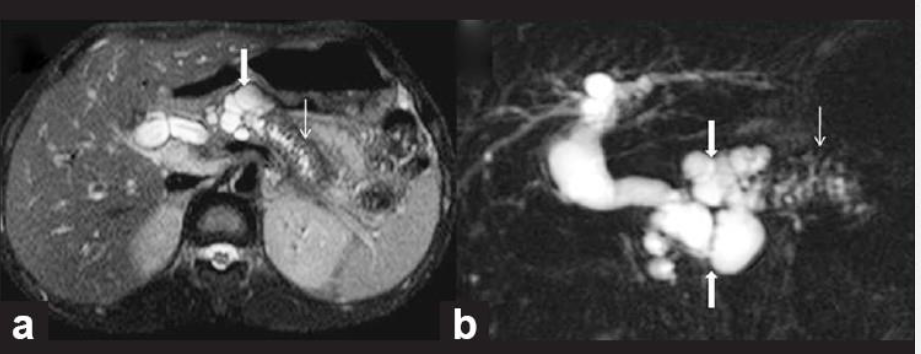

8

Q

מהו הממצא

A

IPMN

הרחבה של צינור הלבלב יחד עם ציסטה, מדובר בציסטה גידולית

How well did you know this?